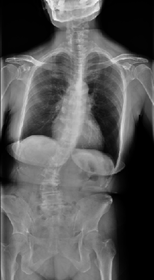

思春期特発性側弯症が高度に進行した症例です。最大側弯角度は113°であり、100°を超える側弯の手術は一般的に神経合併症が危惧されます。神経合併症を極力防ぐため、また侵襲を低減する目的で、同じ入院期間に2回に分けて段階的に矯正手術を行いました。1回目に最も側弯の強い箇所に対して側方から椎体間解離を行い、2回目に後方から全体のバランスが良くなるように慎重に矯正固定術を施行しています。

神経合併症はなく、術後の最大側弯角度は15°に改善(矯正率:87%)、背中の大きなコブも無くなっているのが分かります(赤矢印)。神経合併症が発生しないように慎重に手術を行うのは当然ですが、側弯を治すだけでなく横から見た姿勢を治すことにも留意しています。